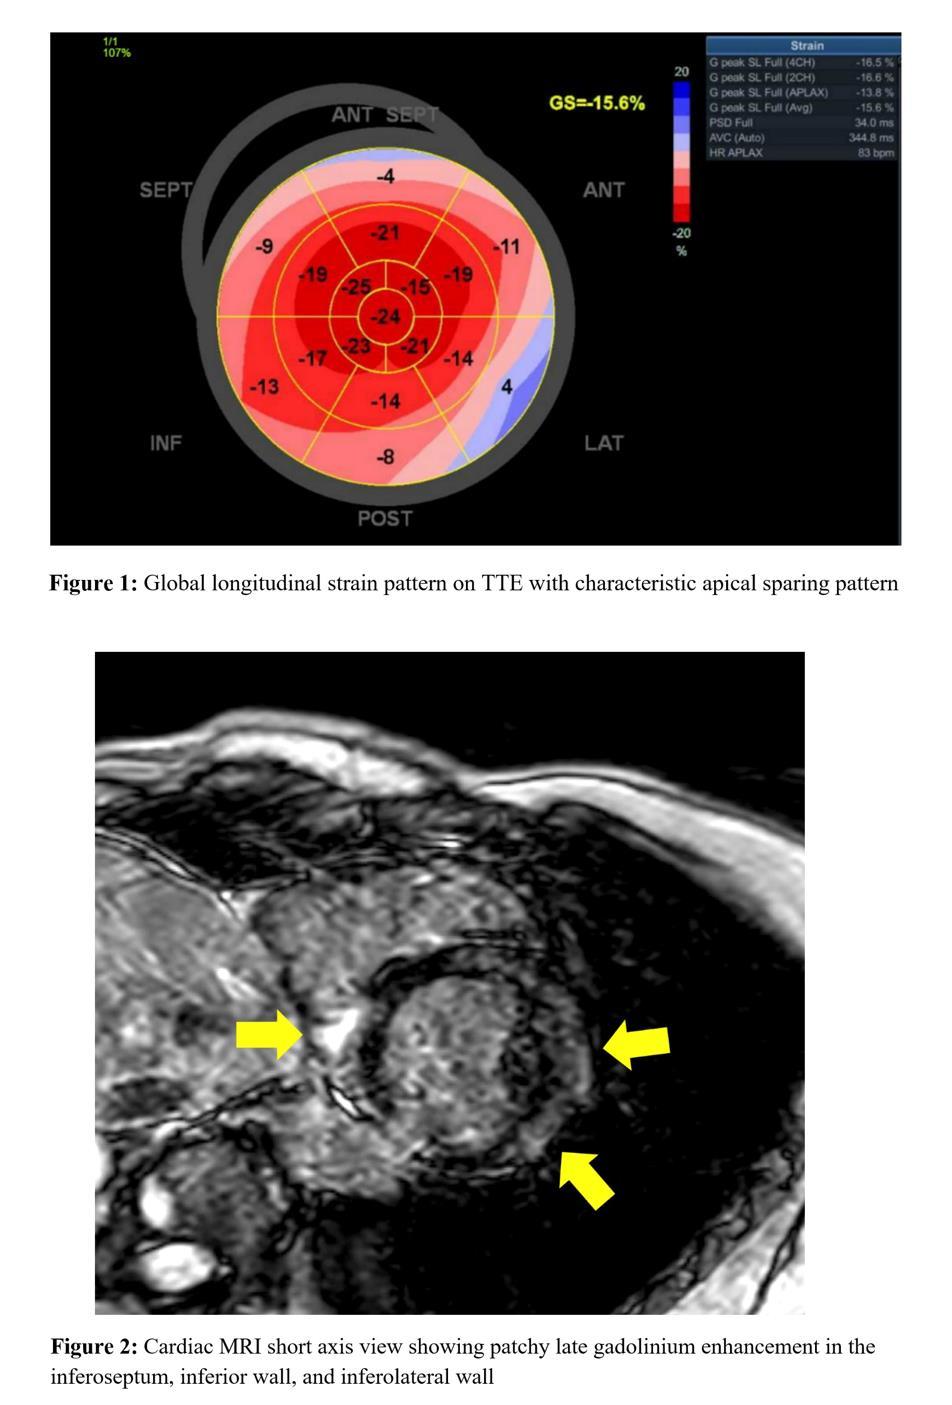

JUNGLE JUICE INDUCED MYOCARDIAL INJURY: CHRONIC USE AND NEW VARIATIONS OF NITRITE PRODUCTS

Matthew Baer1, James Choi1, Vahid Namdarizandi1, Sandra Maria Soler3

1Mount Sinai Morningside-West Hospitals, Icahn School of Medicine at Mount Sinai, New York, NY, United States;

2James J. Peters Department of Veterans Affairs, United States Department of Veteran Affairs, Bronx, NY, United States Presented at the American College of Cardiology (ACC) Annual Meeting that was held in Atlanta, Georgia, United States from April 6-8, 2024.

BACKGROUND/INTRODUCTION: Jungle Juice is an alkyl nitrite derivative commonly purchased at supplement stores and used as an illegal inhalant. Limited case reports highlighting myocardial injury from chronic use have been published, along with recognizing newer variations of illegal nitrites.

CASE PRESENTATION: A 60-year-old male with hyperlipidemia presented after a syncopal episode. He presented multiple times prior for syncope, which was attributed to chronic, daily use of a nitrite supplement, Jungle Juice, and was treated with methylene blue each time. He now admitted to taking a different brand of Jungle Juice. Troponin 1300, blood pressure 195/91, and EKG unremarkable, with myocardial injury attributed to demand ischemia from rebound sympathetic response and coronary vasospasm from chronic Jungle Juice use. No percutaneous intervention was attempted, as he denied chest pain and was asymptomatic when seen by Cardiology. Myocardial perfusion scan showed minimal apical and anterolateral ischemia with reversible hypoperfusion; ejection fraction of 68%. Chronic and potentially lethal doses of nitrites from inhalants may lead to coronary artery vasospasm with increased sympathetic tone similar to the reaction seen with rebound angina from chronic nitrate tolerance. Although nitrite use usually presents with hypotension and syncope due to methemoglobinemia (current literature highlights cases after single episode use), this patient experienced rebound sympathetic response immediately after presentation leading to myocardial injury. This may be due to his daily use, leading to “withdrawal” and a depletion of nitric oxide availability. Further use by this patient and recurrent episodes of cessation, will likely lead to more myocardial demand ischemia and possible cardiac arrest. Newer variations in nitrites also contain more potent concentrations and novel compounds, with patients presenting “non-traditionally” after use.

CONCLUSION: Jungle Juice contains derivatives of nitrite inhalants that are becoming increasingly diverse in supplement stores. It is important to identify the frequency and type of use in patients to properly identify symptoms and order further cardiac workup.